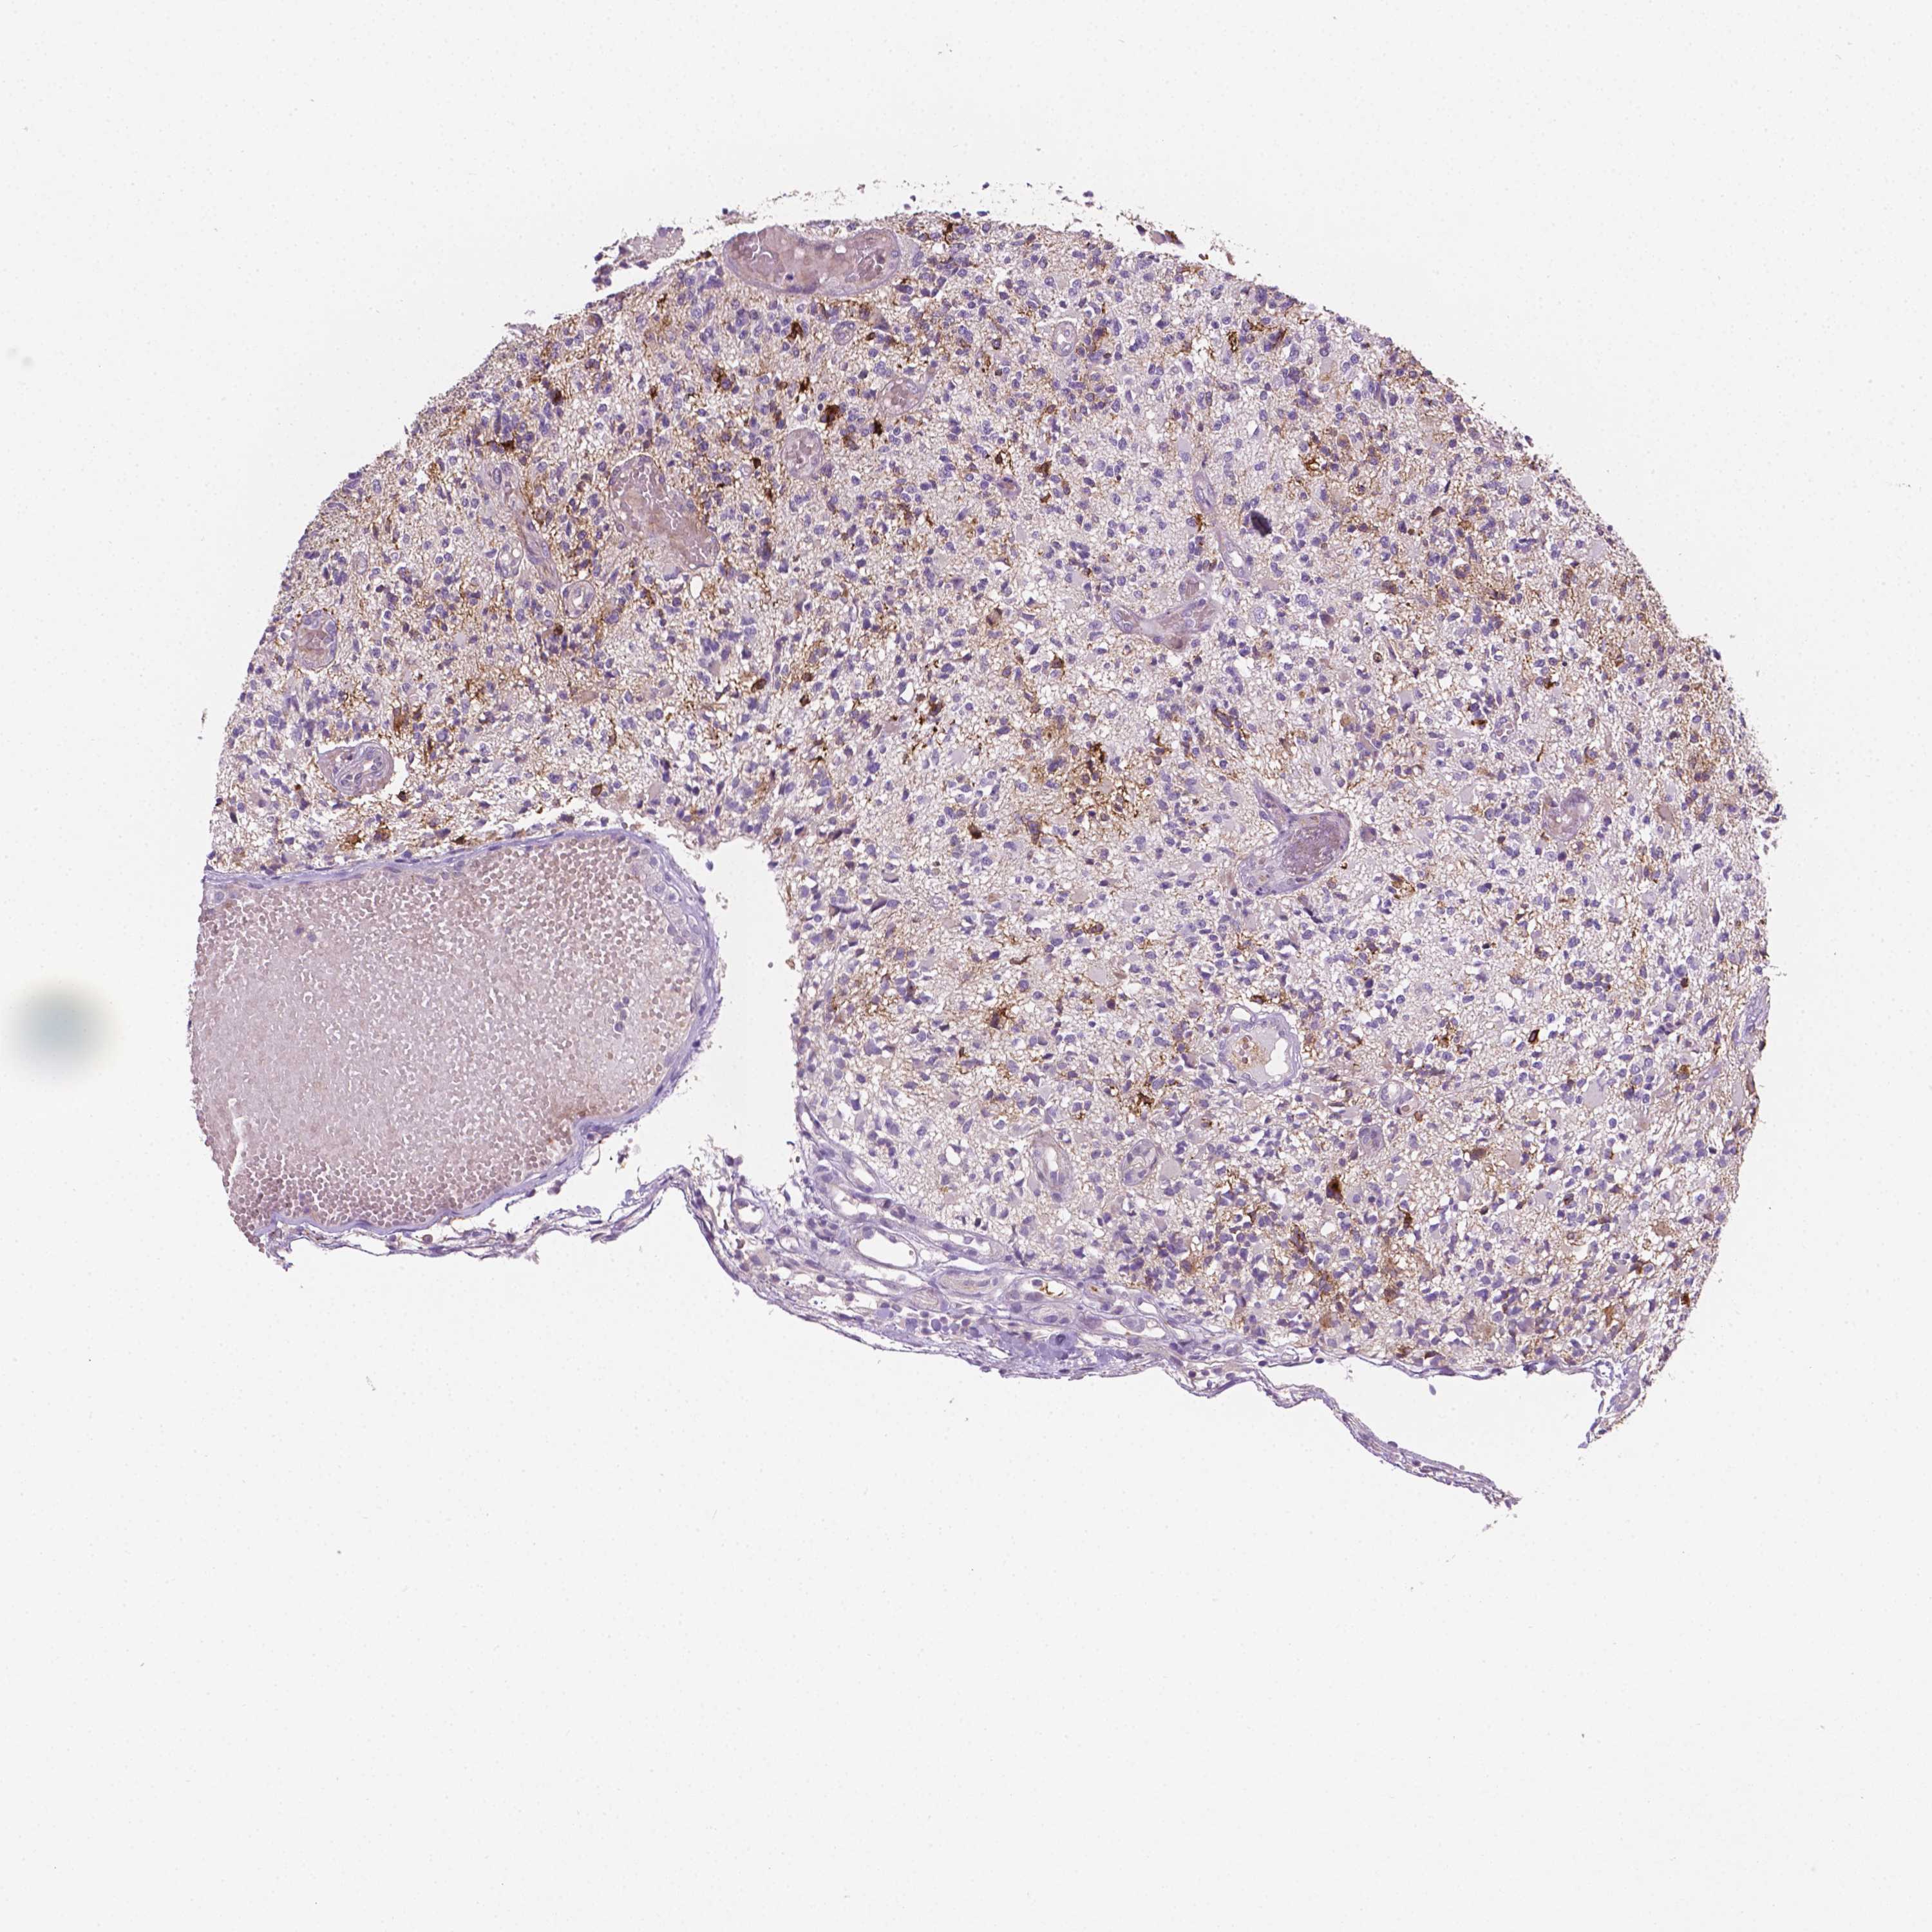

GLIOMA - Protein expressioni

A mouse-over function shows sample information and annotation data. Click on an image to view it in a full screen mode. Samples can be filtered based on level of antibody staining by selecting one or several of the following categories: high, medium, low and not detected. The assay and annotation is described here.

Note that samples used for immunohistochemistry by the Human Protein Atlas do not correspond to samples in the TCGA dataset.

Antibody stainingi

Antibody staining in the annotated cell types in the current human tissue is reported as not detected, low, medium, or high, based on conventional immunohistochemistry profiling in selected tissues. This score is based on the combination of the staining intensity and fraction of stained cells.

Each image is clickable and will lead to virtual microscopy that enables deeper exploration of all samples and also displays staining intensity scores, fraction scores and subcellular localization as well as patient and tissue information for each sample.

Glioma, malignant, High grade

Glioma, malignant, Low grade

Glioma, malignant, NOS